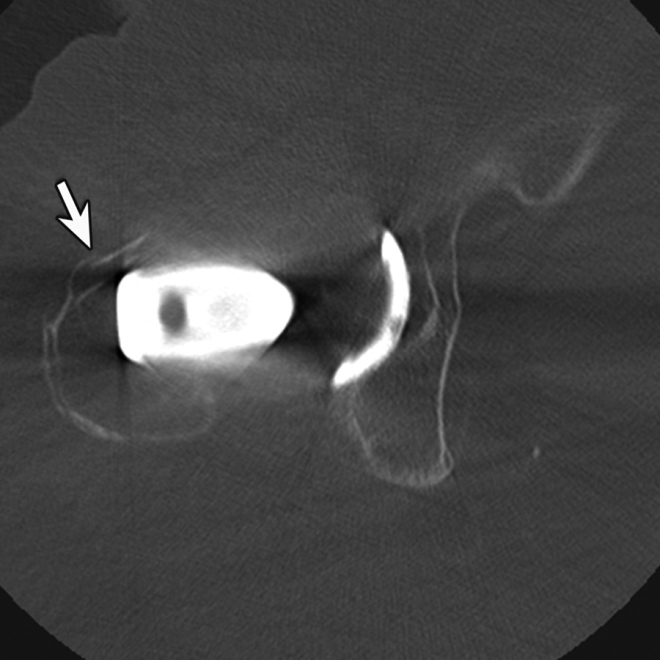

Hardware failure

Radiographs remain the gold standard for assessing the integrity of implanted hardware; however, CT may be useful in particular cases. Prior to complete fracture union, hardware failure poses a significant impediment to fracture healing, and, in fact, may be an indicator of fracture non-union as chronic mechanical stress at the persistent fracture site results in hardware fracture. Consequently, CT examinations for fracture healing should also include a close inspection of surgical hardware, particularly in cases of non-union.

Just as with the immediate post-operative setting, CT is the modality of choice for evaluating complications related to spinal fusion. Screw fracture may occur in up to 25% of patients (Figure 13) (Ohashi, 2009; Lonstein, 1999). As with all cases of hardware failure, the imaging findings should be correlated with patient symptoms as not all hardware complications relate to current clinical symptoms. CT can be useful for the detection of polyethylene dislocation, which may occur in shoulder, hip and knee arthroplasties, and may be difficult to detect on radiographs (Figure 14) (Clarke, 2004).

Figure 11 Figure 12 Figure 13 Figure 14

Hardware infection Small particle disease Hardware failure Liner displacement

Hardware Failure. Sagittal multiplanar reformation demonstrates fractured pedicle screw in patient with treated vertebral compression fracture and sudden onset of worsening back pain.